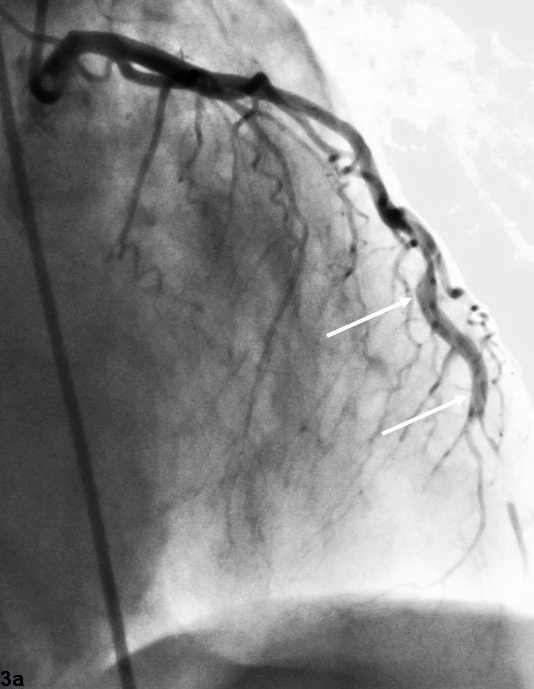

Abstract PDF ECG 1 Angio 1 Angio 2 Angio 3 Angio 4 ECG 2 Table Chart Original File 1 2 3 4 5 6 Reply to reviewer Fig. 1. ECG during myocardial infarction Fig. 2. Coronary angiography of LCA during myocardial infarction Fig. 3. Coronary angiography of LCA during myocardial infarction Fig. 3a. Coronary angiography of LCA during myocardial infarction Fig. 4. Coronary angiography of LCA 2 years after myocardial infarction Fig. 5. Coronary angiography of LCA 2 years after myocardial infarction Fig. 6. ECG 2 years after myocardial infarction Fig. 7. Thrombolytic trials in patients with coronary artery dissection Fig. 8. Flow chart of the study selection process -